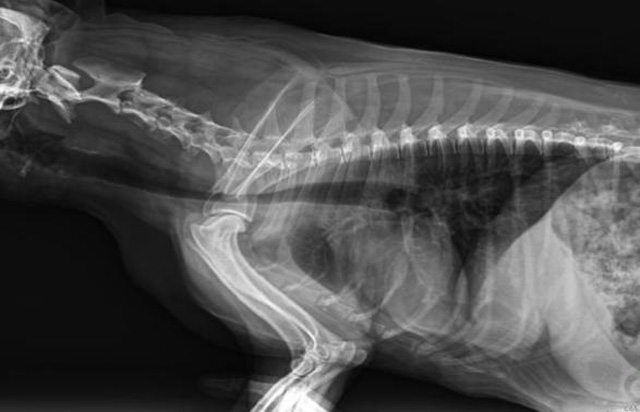

從臨床角度出發,大力發展動態DR,以精準的診斷為小動物保駕護航。寵物DR升級使用雙焦點球管,大尺寸平板探測器,超高頻逆變高壓發生器。醫用纖維板臺面,防止寵物劃傷。寵物DR整機小巧實用,骨略結構和器官位置,分類詳細,運算更快,讓拍攝條件更科學,有助于提高診斷的準確性和效率。安裝移動非常方便。低輸入電流設計,220伏常規電壓。多品種動物程序設定,滿足各個臨床需求。成像效果顯著,寵物不能言語表達,導致誤診率居高不下。寵物診療均以經驗診斷為主的方式,確保最小化輻射降低對醫生及動物的影響。以滿足精細化的寵物醫療需求,成為診斷寵物內外科疾病的必備工具。使醫院更有競爭力,為醫院創收增光添彩。